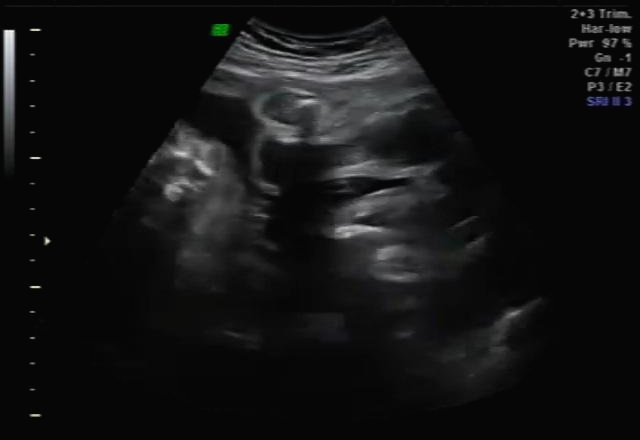

임신 30주 초음파 검사

30주 차! 다행히? 다시 성별반전은 없는 것 같아요~ 허벅지 뼈? 길이 봐주시면서 스쳐갔는데 다리사이에 아무것도 보이지 않네요~